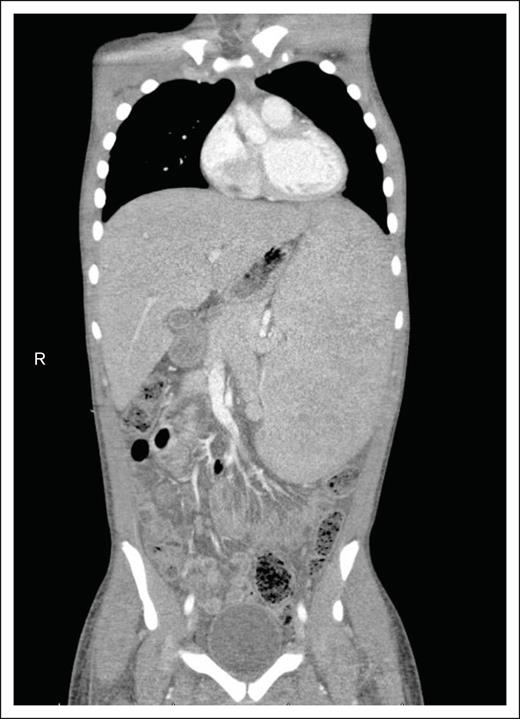

In terms of imaging, contrast-enhanced CT and PET/CT scans are commonly used to evaluate whole-body metabolic and morphologic presence of disease, similar to children and adolescents with other NHL (Figure 2).68 Use of magnetic resonance imaging (MRI) and PET/MRI have also been described; however, similar to other lymphomas, they are recommended as alternative or adjunctive imaging modalities due to the superior sensitivity and specificity of CT and CT/PET in detecting both nodal and extranodal disease.69,70 CT and PET/CT each have pros and cons.71 CT scans can miss extranodal disease, particularly relevant for HSTCL. PET/CT scans have not been studied as extensively in pediatric NHL compared with adults and other malignancies and may be inadequate for response assessment alone.72,73 CTs usually show an enlarged liver and spleen without discrete lesions, whereas PET/CT may show avidity in the liver, spleen, and bone marrow.71,74

Imaging findings in HSTCL. CT scans of the abdomen and pelvis typically reveal massive hepatosplenomegaly, displacing other organs, with minimal enlarged lymph nodes. R, right side of the body.